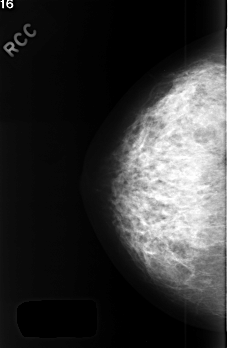

C_0412_1.RIGHT_CC

RIGHT_CC LINES 4512 PIXELS_PER_LINE 2968 BITS_PER_PIXEL 12 RESOLUTION 50 NON_OVERLAY